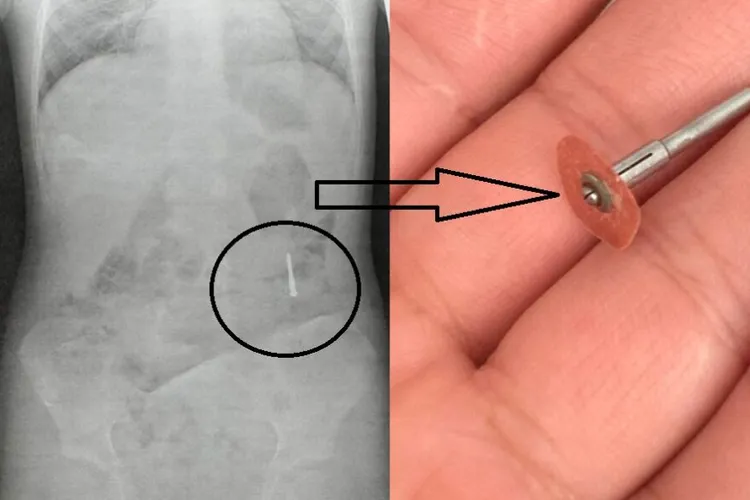

Incident grav într-un cabinet stomatologic: freză metalică scăpată în gura unui copil

Incident stomatologic grav, copil la urgențe. Un copil de 5 ani din Iași a ajuns la spital după ce a înghițit o freză metalică în timpul unei consultații stomatologice. Incident stomatologic grav, copil la urgențe Incidentul a avut loc în cabinetul unui dentist, care le-ar fi spus părinților că micuțul a înghițit doar o hârtie abrazivă, ce urma să fie eliminată fără probleme. Citește și: După ce PSD a trimis la CCR un ex-tablagiu, Nicușor Dan a nominalizat un universitar fără pată Îngrijorați, părinții l-au dus la Spitalul „Sf. Maria”, unde radiografia a arătat prezența unui obiect metalic de peste 2 centimetri. Familia susține că este vorba despre o freză dentară scăpată accidental în timpul tratamentului. Continuarea, în Ziarul de Iași